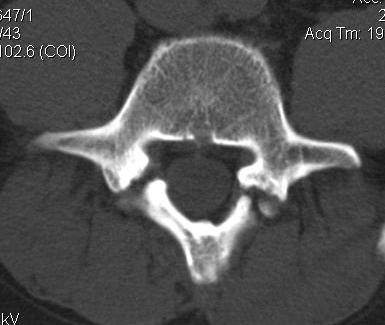

CT scan

Technique

- reverse gantry

Indication

- perform instead of obliques

- oblique x-rays have high radiation dose with little extra information compared with CT

Spondylolysis

Definition

- radiolucent defect of pars

Types

- acute - narrow gap & irregular edges

- pars elongated & thinned

- chronic - wide gap with smooth sclerotic edges